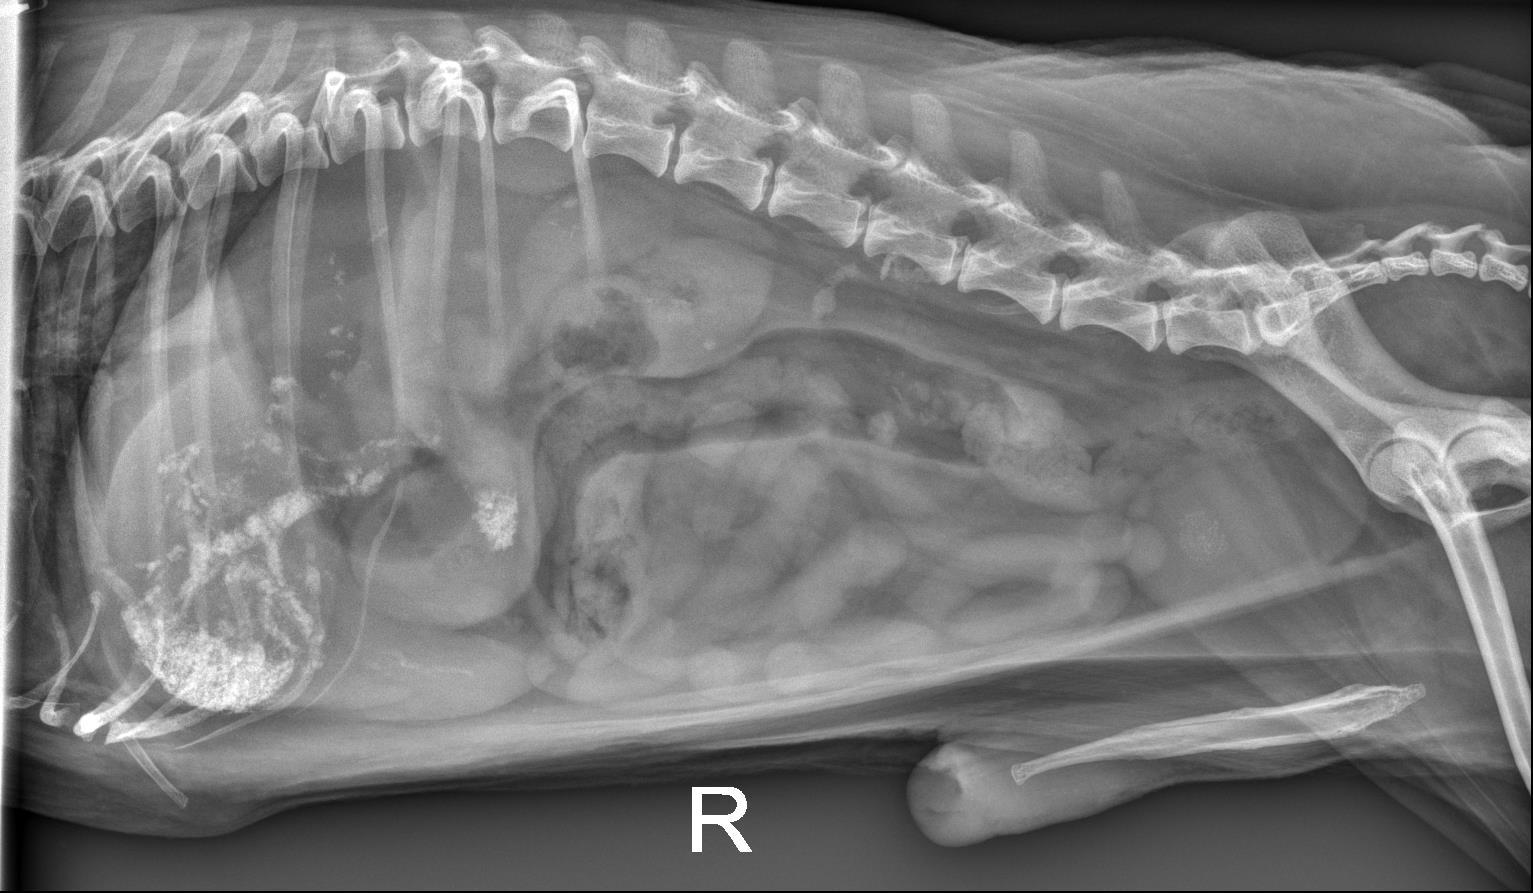

Abdomen - ventrodorsal and lateral radiographs are available for interpretation.

Abdominal serosal detail is normal.

There are numerous, stippled to angular, mineral opaque foci in the gallbladder and throughout the hepatic parenchyma which are suspected to be within the biliary tract, given the linear/arborized appearance. The liver is mildly enlarged with rounded margins extending beyond the costal arch. Best identified on the ventrodorsal radiograph, there is focal accumulation of this mineral superimposed with the proximal portion of the descending duodenum.

The stomach contains a small to moderate volume of gas and homogeneously soft tissue/fluid opaque material. The small intestines contain a small volume of homogeneously soft tissue/fluid opaque material and scant volumes of gas. The colon contains a small volume of heterogeneous fecal material and gas.

The kidneys have mildly undulant margins and contain multiple punctate to linear mineral opacities. There are numerous, small, well-marginated, round, faintly mineral opaque foci within the urinary bladder. The spleen is normal.

There is a small volume of mineral opaque material superimposed with multiple small intestinal segments on the ventrodorsal radiograph. On the lateral radiograph, this material is present superimposed with the retroperitoneal space at the level of the fourth lumbar vertebra.

Severe cholelithiasis and choledocholithiasis with suspected accumulation of mineral opaque material at the level of the duodenal papilla likely resulting in at least partial obstruction, given the reported clinical signs and labwork abnormalities. The planned abdominal ultrasound is recommended for further evaluation.

- Moderate hepatomegaly is non-specific, but likely represents a benign processes such as vacuolar degeneration or nodular hyperplasia. Malignancy (such as infiltrative round cell neoplasia) is considered less likely.

- Bilateral chronic renal degenerative changes and nephrolithiasis. Cystolithasis.

– The appearance of the gastrointestinal tract is most consistent with a non-specific gastroenteritis, given the reported vomiting.

– The mineral opaque material superimposed with the right caudal abdomen at the level of the fourth lumbar vertebra is suspected to represent mineralization of the extra-abdominal soft tissues.